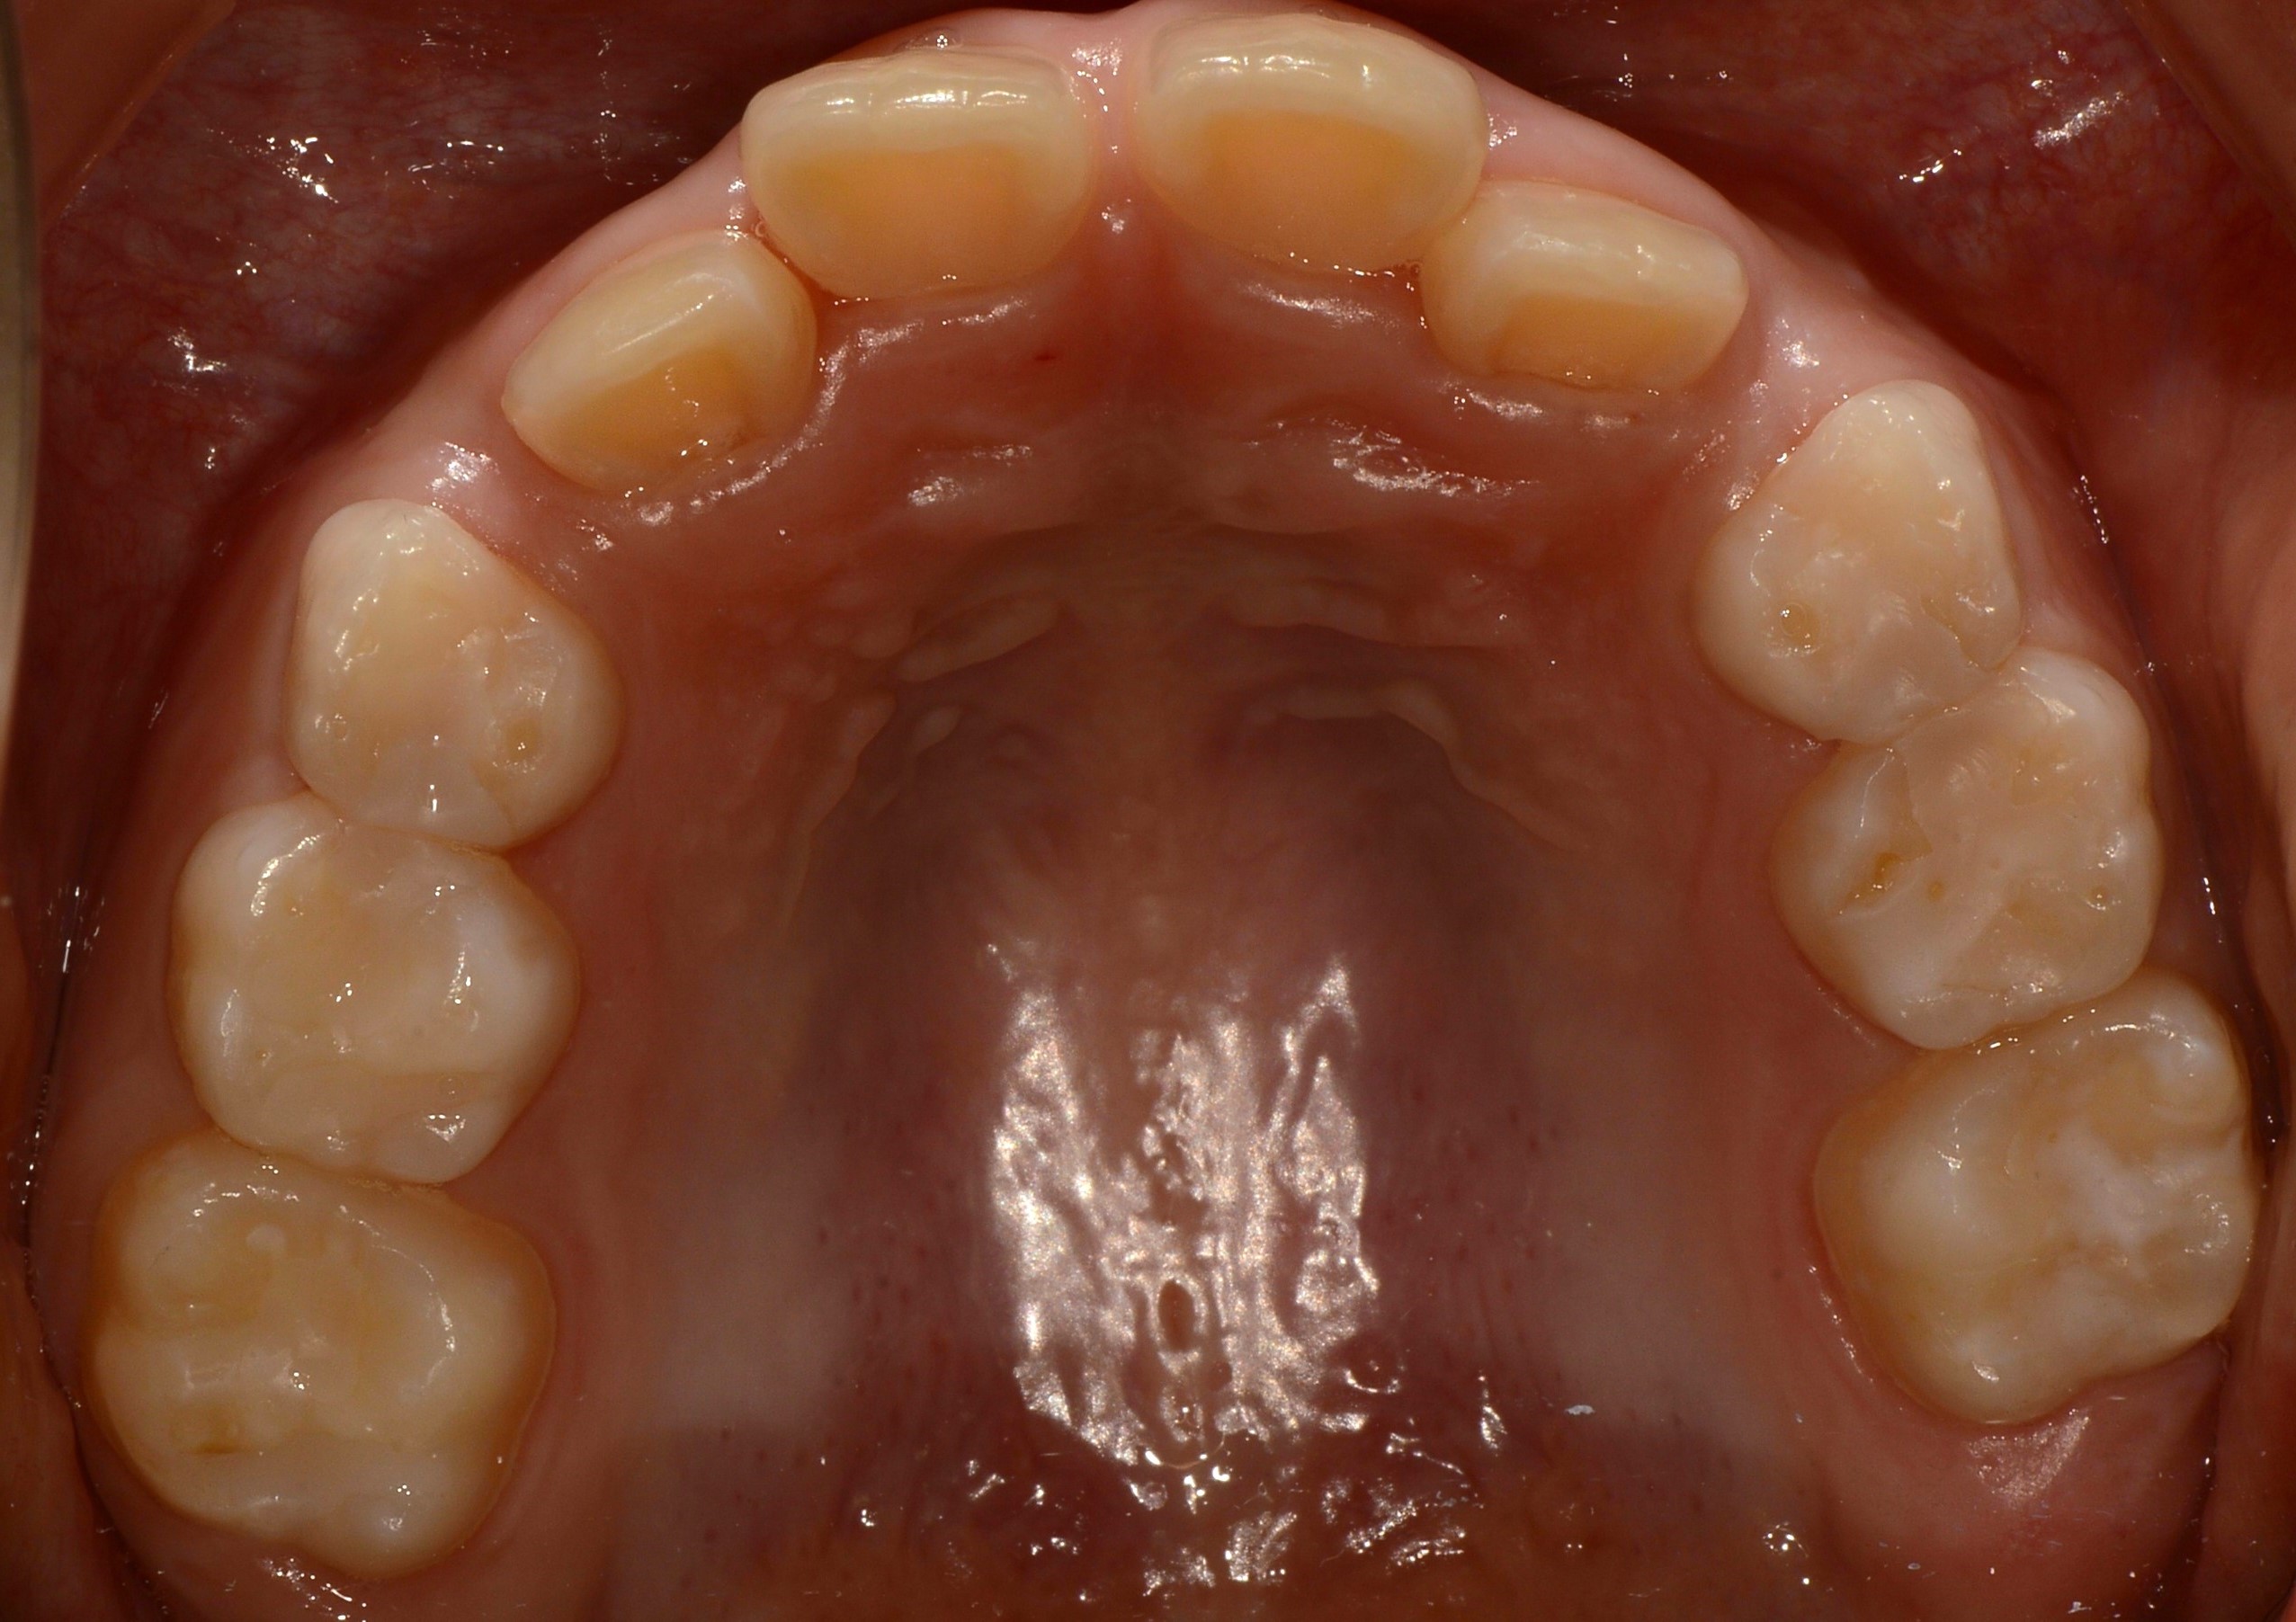

치료 전 사진입니다.